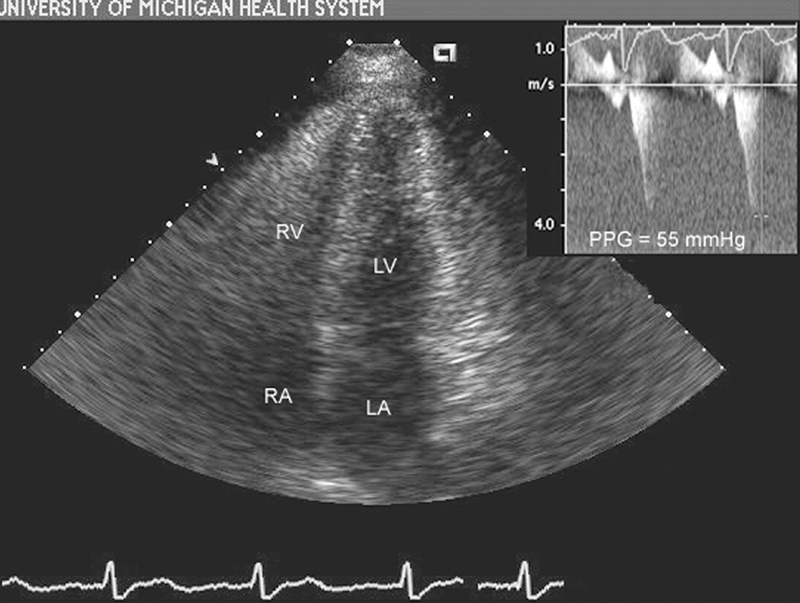

فحوصات تشخيصية لبعض امراض القلب والشرايين التاجية